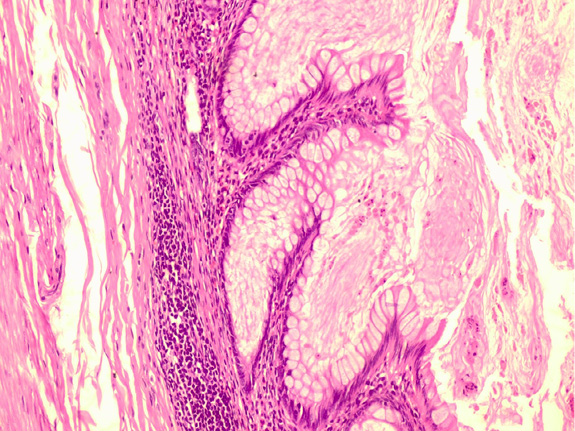

Pathologically, the appendix lumen diameter was 1.7 cm in the widest area. The appendix’s long axis was 7.5 cm. Mucoid material was observed in the lumen. The pathologic diagnosis was low-grade appendiceal mucinous neoplasm (appendiceal villous adenoma). Villiform mucinous epithelial proliferation was observed to replace the normal appendix mucosa [Figure 2]. It was observed that lymphoid tissue decreased In lamina propria and was replaced with fibrotic connective tissue [Figure 3]. Villiform mucinous epithelial proliferation appears to be composed of long mucinous epithelial cells with a low degree of nuclear atypia [Figure 4].

Figure 3. In the lamina propria, it is observed that lymphoid tissue decreases, instead, fibrotic connective tissue passes